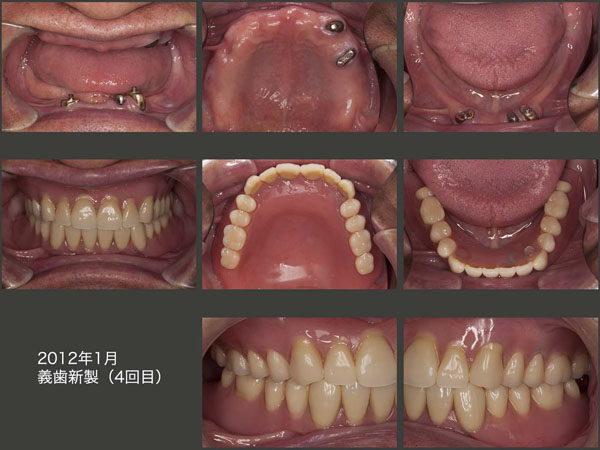

ここで,1983年の第1回から2012年の第4回までの新義歯製作時の正面観を比較してみる.

83年の咬合はどう見ても高いような気がする.91年にかけて,義歯を壊しながら徐々に生体が咬合を低くしているのが見てとれる.咬合が低下することは良くないと信じていたので,92年に咬合を挙上した義歯を新製した.また,01年にかけて徐々に咬合が低くなったが,同様な考えから01年に咬合を挙上した義歯を新製した.そしてまた,11年にかけて右上4,5の歯を失いながら咬合は低くなっていった.さすがに,12年の時は,咬合を挙上するのは危険であるという認識があったので,咬合高径を上げることはなかった.